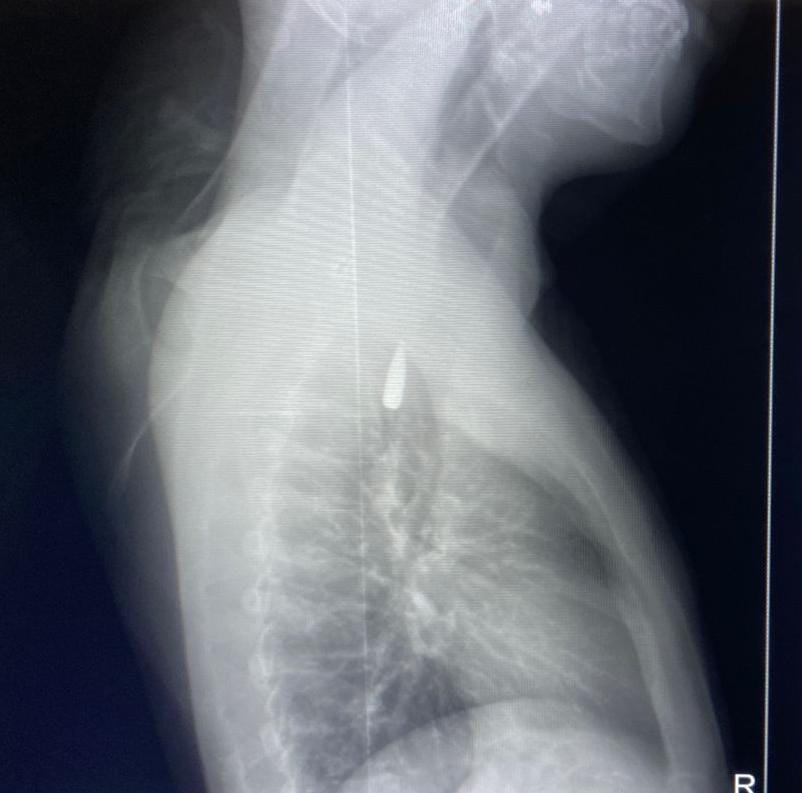

وأوضح تامر عبد الله أن المريض كان قد تعرض لإصابة بطلق ناري في الرأس منذ فترة، استقر المقذوف على إثرها داخل تجويف القفص الصدري قرب الشريان الأورطي، وهو أكبر وأهم شرايين الجسم والمسؤول عن تغذية جميع الأعضاء الحيوية.

وأضاف أن الفريق الطبي، رغم دقة الحالة وتعقيدها، نجح في استخراج المقذوف بأمان بعد عملية جراحية نادرة استمرت عدة ساعات داخل المستشفى الجامعي الجديد، بتاريخ 21 أكتوبر الحالي، حيث خضع المريض بعدها للرعاية الطبية اللازمة، وحالته حاليًا مستقرة وتحت المتابعة الدقيقة من الفريق المختص.